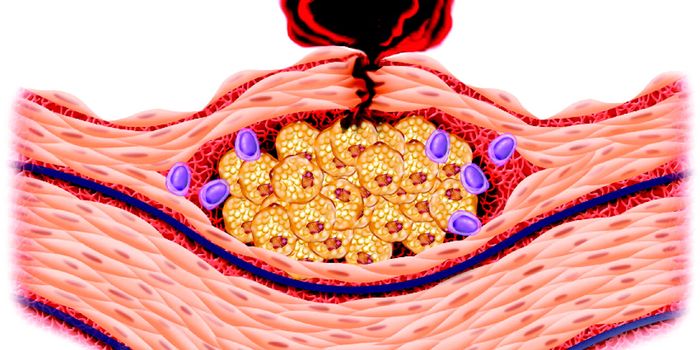

SEP 18, 2022ImmunologyWhen we get a bacterial infection in our skin, our immune system responds. It's been thought that inflammatory cells ...